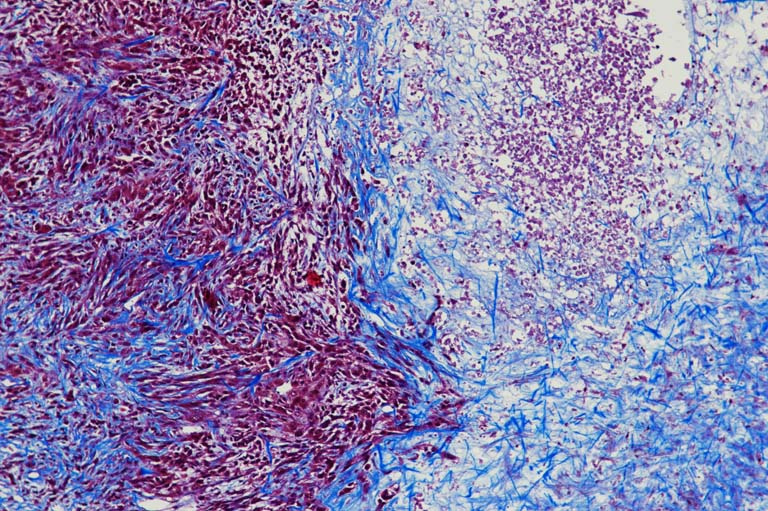

These are images of sections of tumors that have been stained to try and understand what is happening inside the tumor. Using this stain we can tell apart live cells from dead cells and we can see whether the tumor cells have started building up extracellular matrix. In these images you can see how complex the inside of these tumors are--there are pink dense live cells, less dense and more purple dead cells, and there are swaths of blue stained extracellular matrix (specifically collagen). In some of the images the extracellular matrix delineates a border between zones that have dead cells or live cells, whereas in other images, the extracellular matrix completely intertwines with either zone.